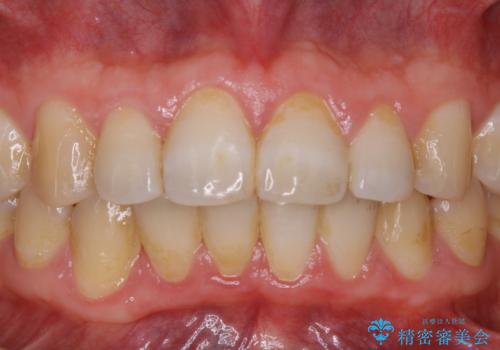

全体的にプラークや歯石が付着していて、歯肉炎が見られました。

状態に合った専門的な器具を使用して、歯質や歯肉へのダメージを抑えながらPMTC(自費クリーニング)60分コースを行いました。矯正治療後の保定装置がワイヤーの場合、フロス・糸ようじが通せないこと、歯ブラシがしずらいことなどにより、歯石プラークなどが付着しやすくなります。そのため専門的な器具による細かいケアを行うことがとても大切です。